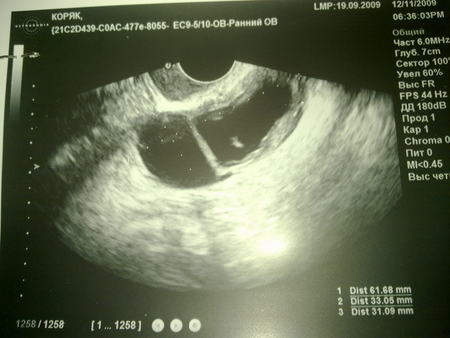

нам тут 7 неделек всего)